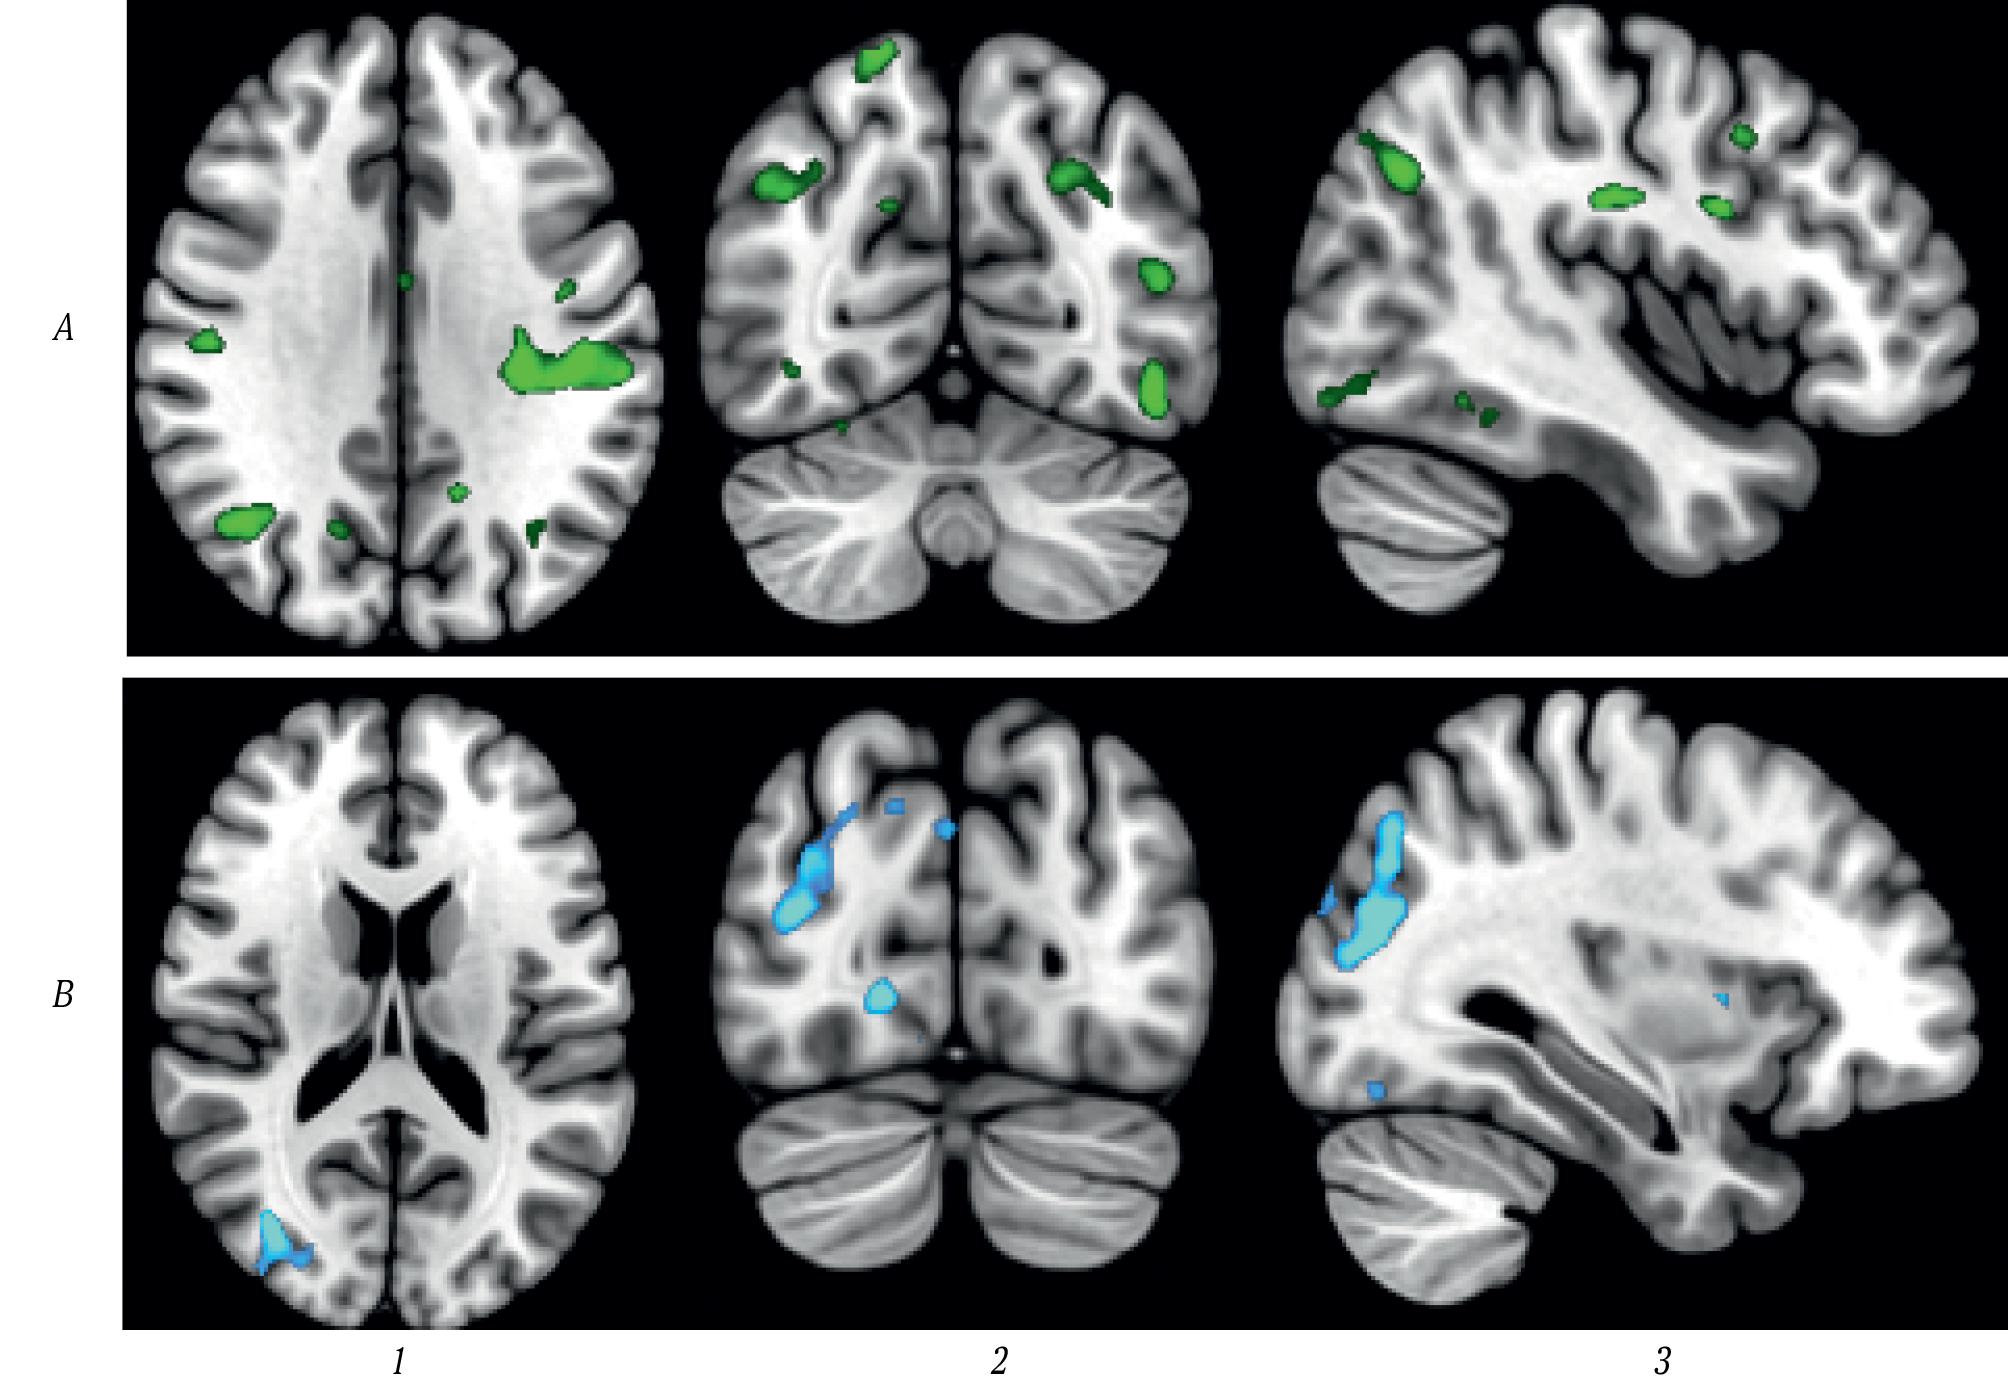

Для получения BOLD-сигнала чаще всего используется эхо-планарная последовательность (градиентное эхо), чувствительная к локальным неоднородностям магнитного поля, которые могут быть вызваны, в частности, таким парамагнетиком, как дезоксигемоглобин, в присутствии которого сигнал снижается [5]. При возникновении возбуждения в определённой зоне головного мозга отмечается локальное усиление кровотока этой области. Это приводит к увеличению концентрации оксигемоглобина и снижению концентрации дезоксигемоглобина. В результате отмечается изменение (повышение) сигнала, которое регистрируется с помощью описанной последовательности. Таким образом, фМРТ позволяет регистрировать распределение нейрональной активности, о которой косвенно судят по изменению сигнала в зависимости от уровня оксигенации крови в сосудах головного мозга. В каждом вокселе регистрируются колебания этого сигнала в течение времени сканирования, которые затем оцениваются с помощью различных статистических инструментов с последующей возможностью группового представления данных, а также межгруппового и внутригруппового анализа (рис. 1).

Рис. 1. Результаты внутригруппового сравнения активации мозга при выполнении когнитивной парадигмы до и после лечения.

А — пациенты, получавшие сосудисто-метаболическую терапию в течение 10 дней (уменьшение активации в надкраевых и ангулярных извилинах, а также зрительной коре); В — пациенты, получавшие плацебо (уменьшение активации только в зрительной коре).

1 – аксиальная проекция; 2 — коронарная проекция; 3 — сагиттальная проекция.